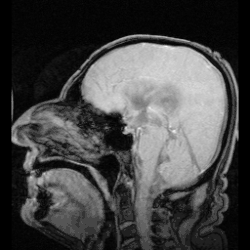

In neuroanatomy, the ventricular system is a set of four interconnected cavities known as cerebral ventricles in the brain.[1][2] Within each ventricle is a region of choroid plexus which produces the circulating cerebrospinal fluid (CSF). The ventricular system is continuous with the central canal of the spinal cord from the fourth ventricle,[3] allowing for the flow of CSF to circulate.[3][4]

The system comprises four ventricles:[5]

- lateral ventricles right and left (one for each hemisphere)

- third ventricle

- fourth ventricle

The four cavities of the human brain are called ventricles.[6] The two largest are the lateral ventricles in the cerebrum, the third ventricle is in the diencephalon of the forebrain between the right and left thalamus, and the fourth ventricle is located at the back of the pons and upper half of the medulla oblongata of the hindbrain. The ventricles are concerned with the production and circulation of cerebrospinal fluid.[7]